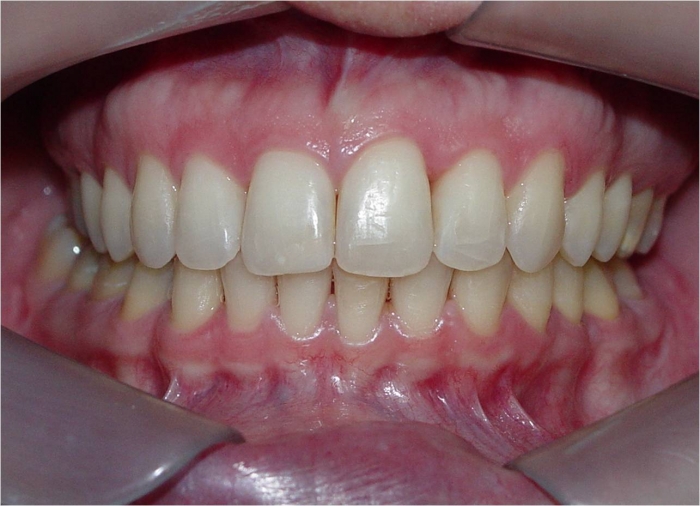

Mordida final